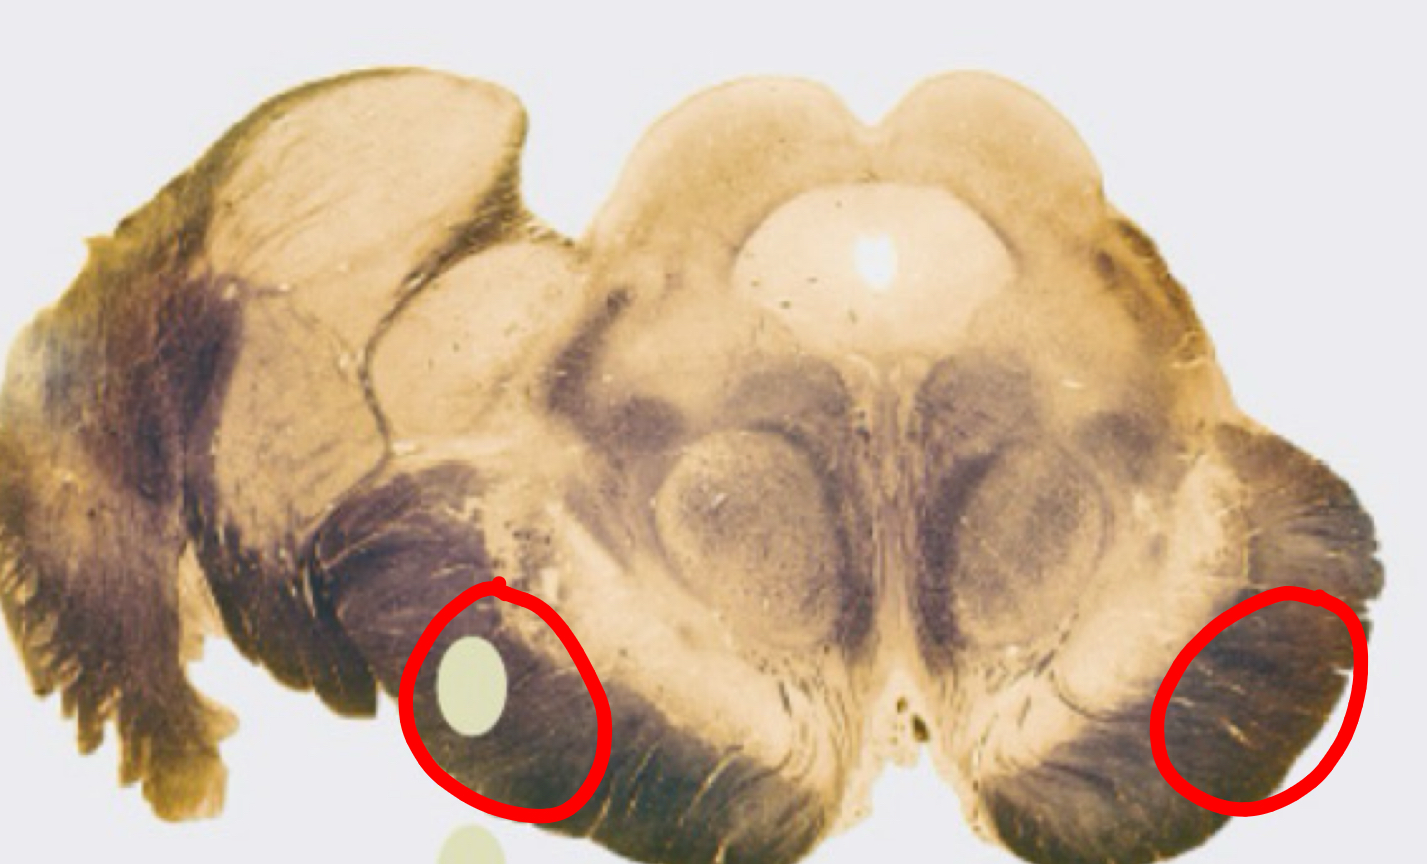

tonsils

flocculus

nodule